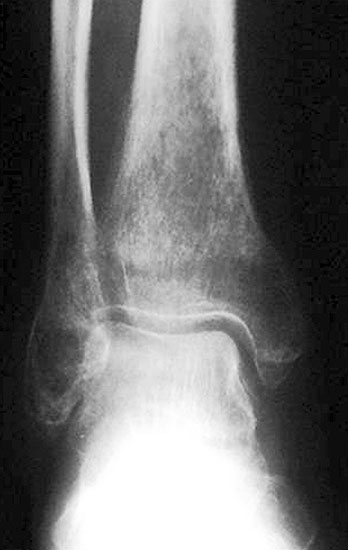

Neben der klinischen Untersuchung (Schwellung, Druck- und Klopfschmerz, Berührungsempfindlichkeit) sind Röntgenuntersuchungen obligat, obwohl sie gerade in den ersten Wochen der Erkrankung kein Korrelat bieten, aber zur differentialdiagnostischen Abgrenzung dienen. Im weiteren Krankheitsverlauf  zeigt sich nach Wochen und Monaten im Röntgen und im CT eine Osteopenie  in der betroffenen Region 8119 (Abb. 4 und 5)

Häufigste Prädilektionsstelle am Fuß stellt der Talus dar, wobei gelegentlich auch der Kalkaneus mitbefallen ist. Einzelne Fallbeschreibungen gibt es zum TKMÖ der Cuneiforme und des Os navikulare (Abb. 1), Studien zum Befall des Vorfußes liegen nicht vor 9.